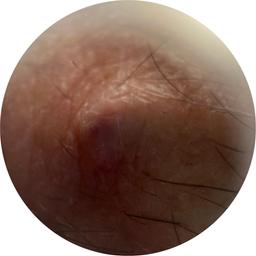

ISIC_7519464

IP_3612490

IL_7662406

Clinical

Field Value

acquisition_day 84

age_approx 70

anatom_site_1 Head and neck

anatom_site_general head/neck

diagnosis_1 Benign

family_hx_mm True

fitzpatrick_skin_type I

image_manipulation instrument only

image_type dermoscopic

lesion_id IL_7662406

patient_id IP_3612490

personal_hx_mm True

sex male